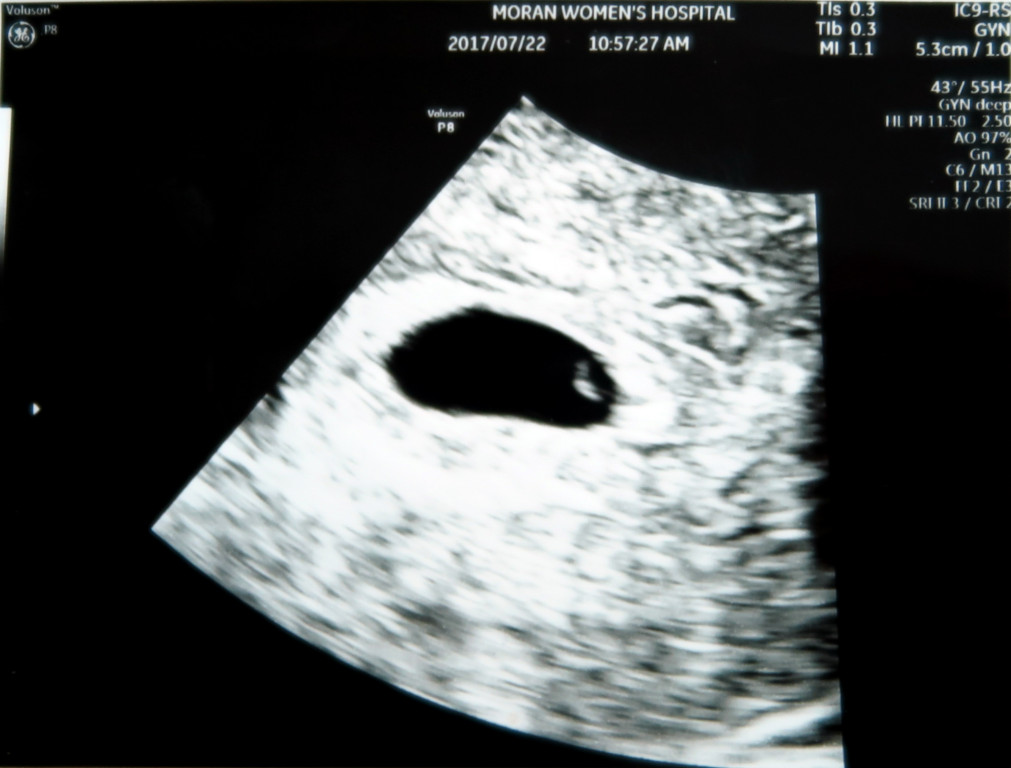

엄마 뱃속에서 콩알만큼 작은 생명이 우리 가족의 일원이 되었다고 신고하네요~